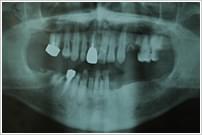

58歳 男性

多数歯欠損。全歯におよぶカリエス。

右下6・7番、左上4・5番を抜歯。

右下6・7番、左上4番、左下3・4・6・7番をインプラント。

全体に歯周治療。

全顎のカリエスは審美性を考慮して、陶材焼付冠で補綴。